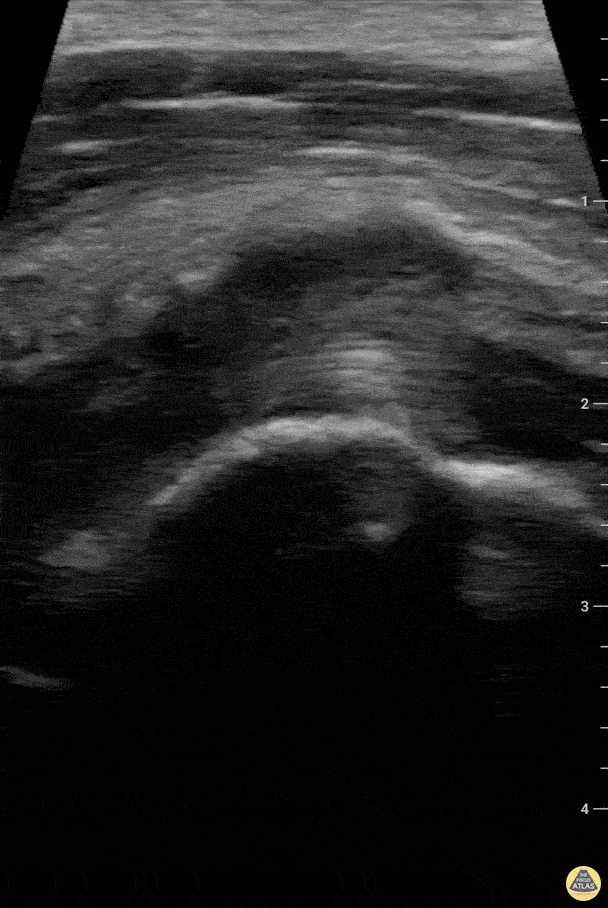

Musculoskeletal - Partial biceps tendon tear - longitudinal

Patient presented with pain localized to the right humeral neck after lifting a heavy object and feeling a "pop" sensation. Negative "Popeye" sign and preserved strength in elbow flexion. Effusion was noted in the bicipital groove on both transverse and longitudinal views. In addition, on longitudinal view the ends of the biceps tendon were noted to remain in tension. Charles Jang, EM PGY-3